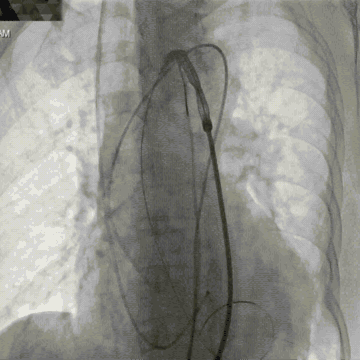

降主血管迂曲,弓部夹角锐利,弓部宽度较短,可谓是“山路十八弯”,得益于TaurusOne®输送系统优异的过弓性能,并在Snare辅助下顺利完成瓣膜系统过弓。

平行导丝技术第二个瓣膜过弓

第二个瓣膜释放过程